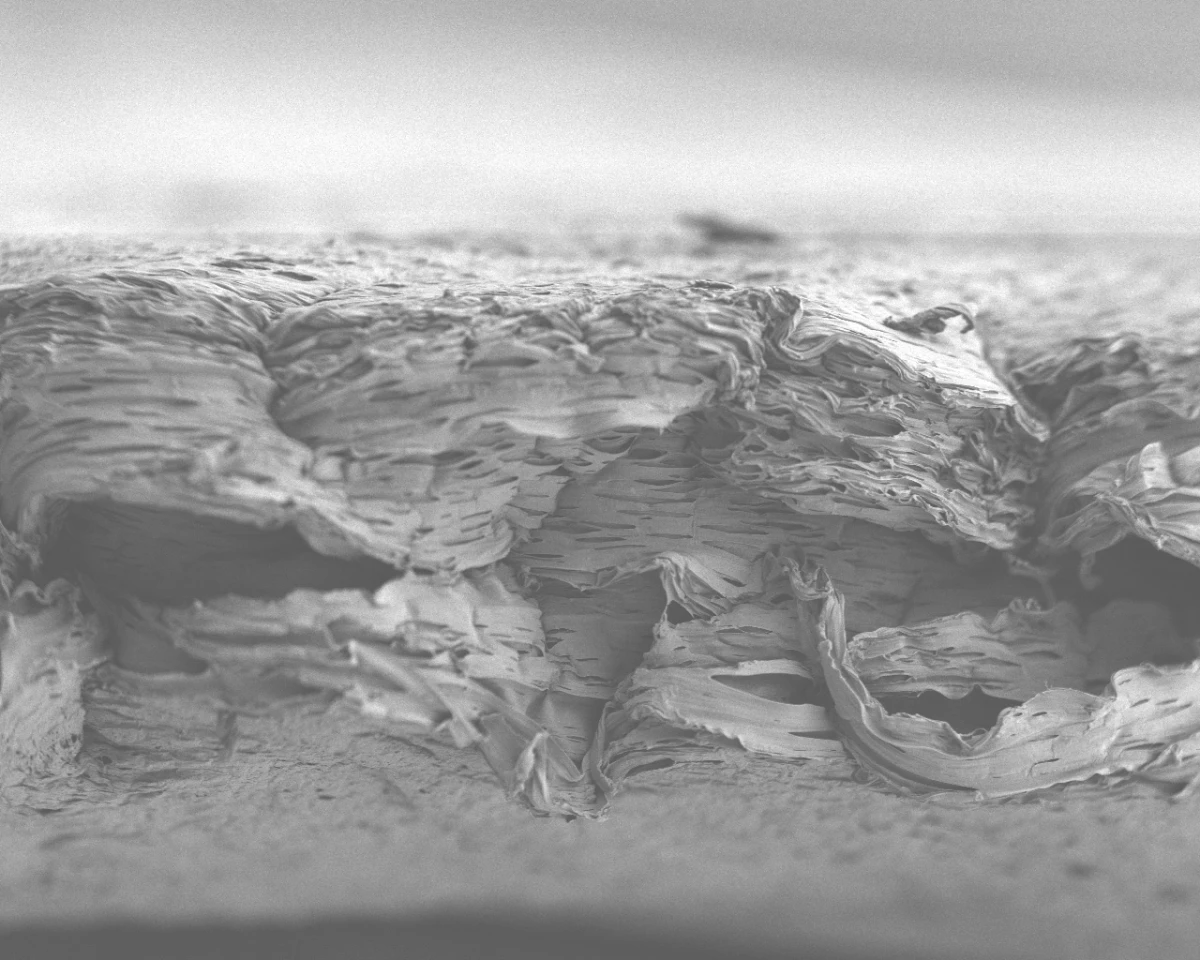

MIT's porous tissue scaffold, as imaged by an electron microscope (Image: MIT)

The 0.1 mm-thick polymer scaffold sheet developed by the scientists from MIT would appear to successfully mimic this biological process, releasing the growth factors in the correct order and quantity, essentially tricking the body into thinking it had initiated the healing process itself. Previous attempts at biomimicry in this area have failed due to an inability to release the growth factors in a natural and controlled fashion, causing the body to clear the factors away from the wound before they could have any substantial healing effect.

The measured release of growth factors is achieved by layering the porous scaffold with around 40 layers of BMP-2, followed by another 40 layers of PDGF. Once the layering process is complete, medical practitioners can cut out segments of the scaffold, tailoring the treatment to fit any size of wound. Furthermore, once the treatment has run its course and the bone has been regrown, the biodegradable scaffold is safely adsorbed into the body, leaving no harmful traces as a by-product of the procedure.